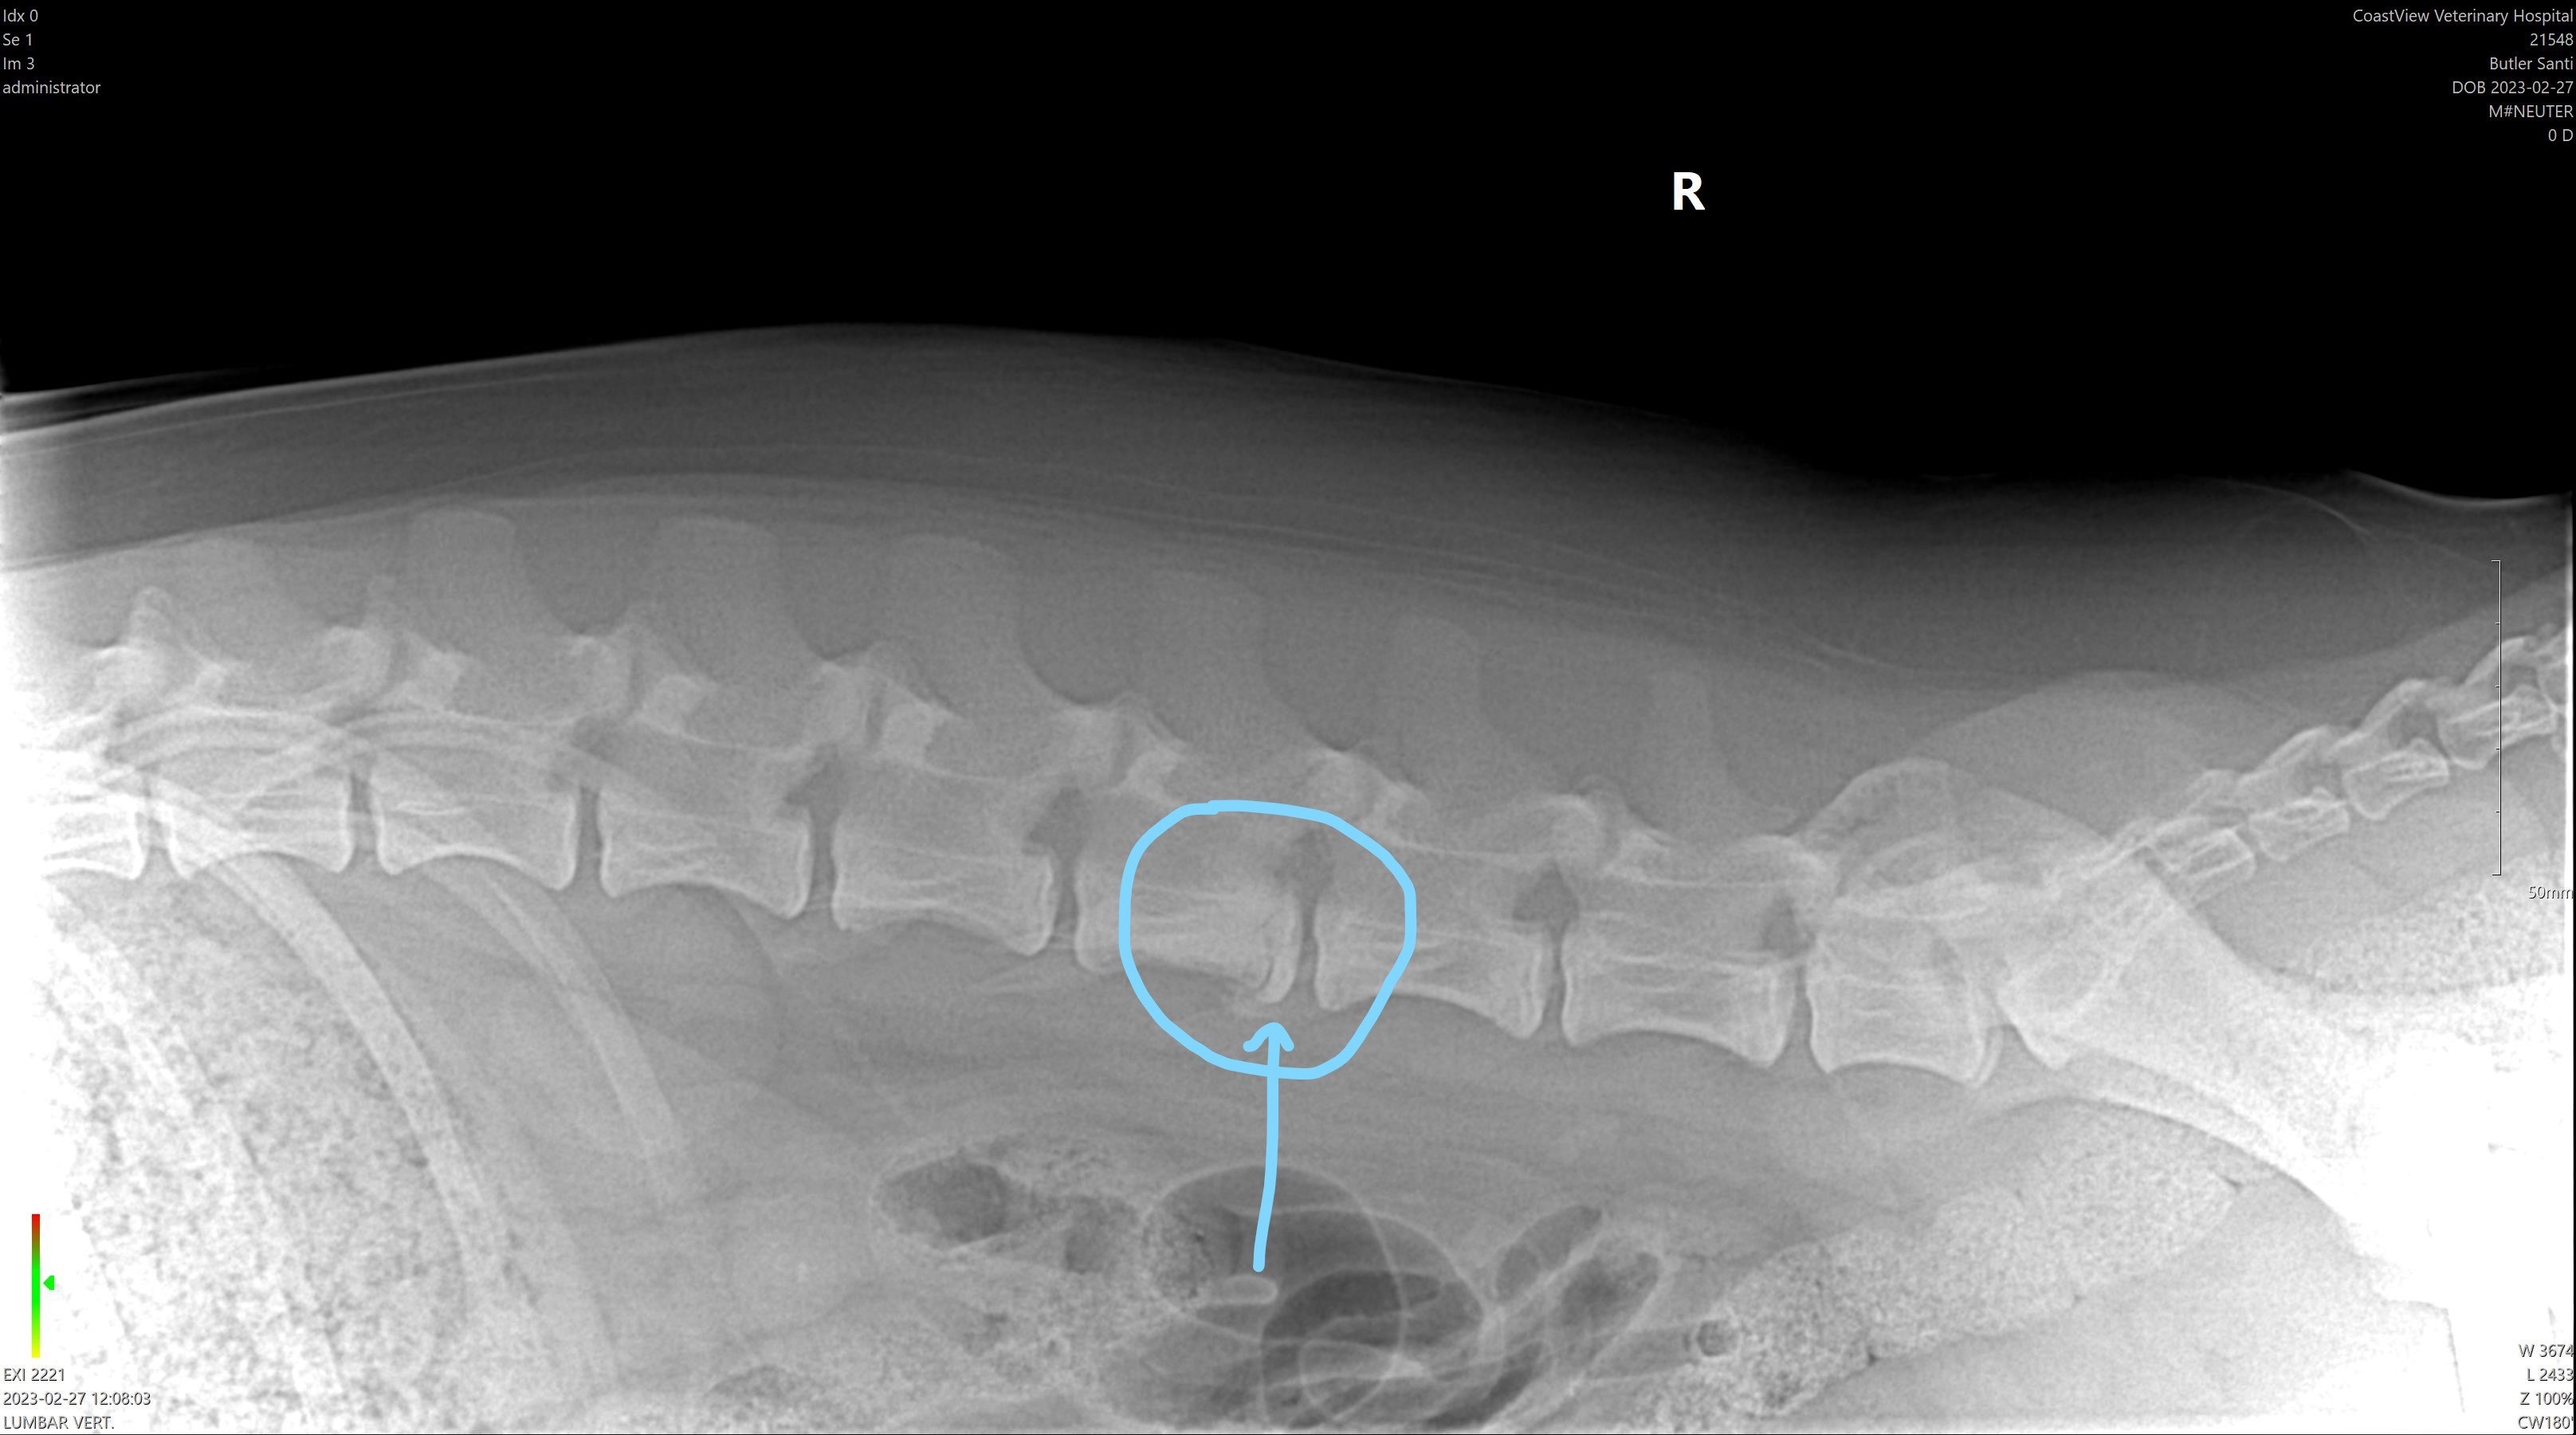

It's likely that Santi has Physitis, an infection of the growth plate of the vertebrae. This is causing him significant daily pain.

An x-ray from two years ago shows evidence of this, however, the vet that we were seeing at the time believed that it was an old fracture and, if I'm being quite honest, acted like I was ridiculous for being concerned about it, so I didn't pursue it further at the time. I feel absolutely awful knowing that this is something that we could have treated years ago, and that Santi has been living in pain for so long. Thankfully, our current vet is wonderful and is working hard to find solutions for us.